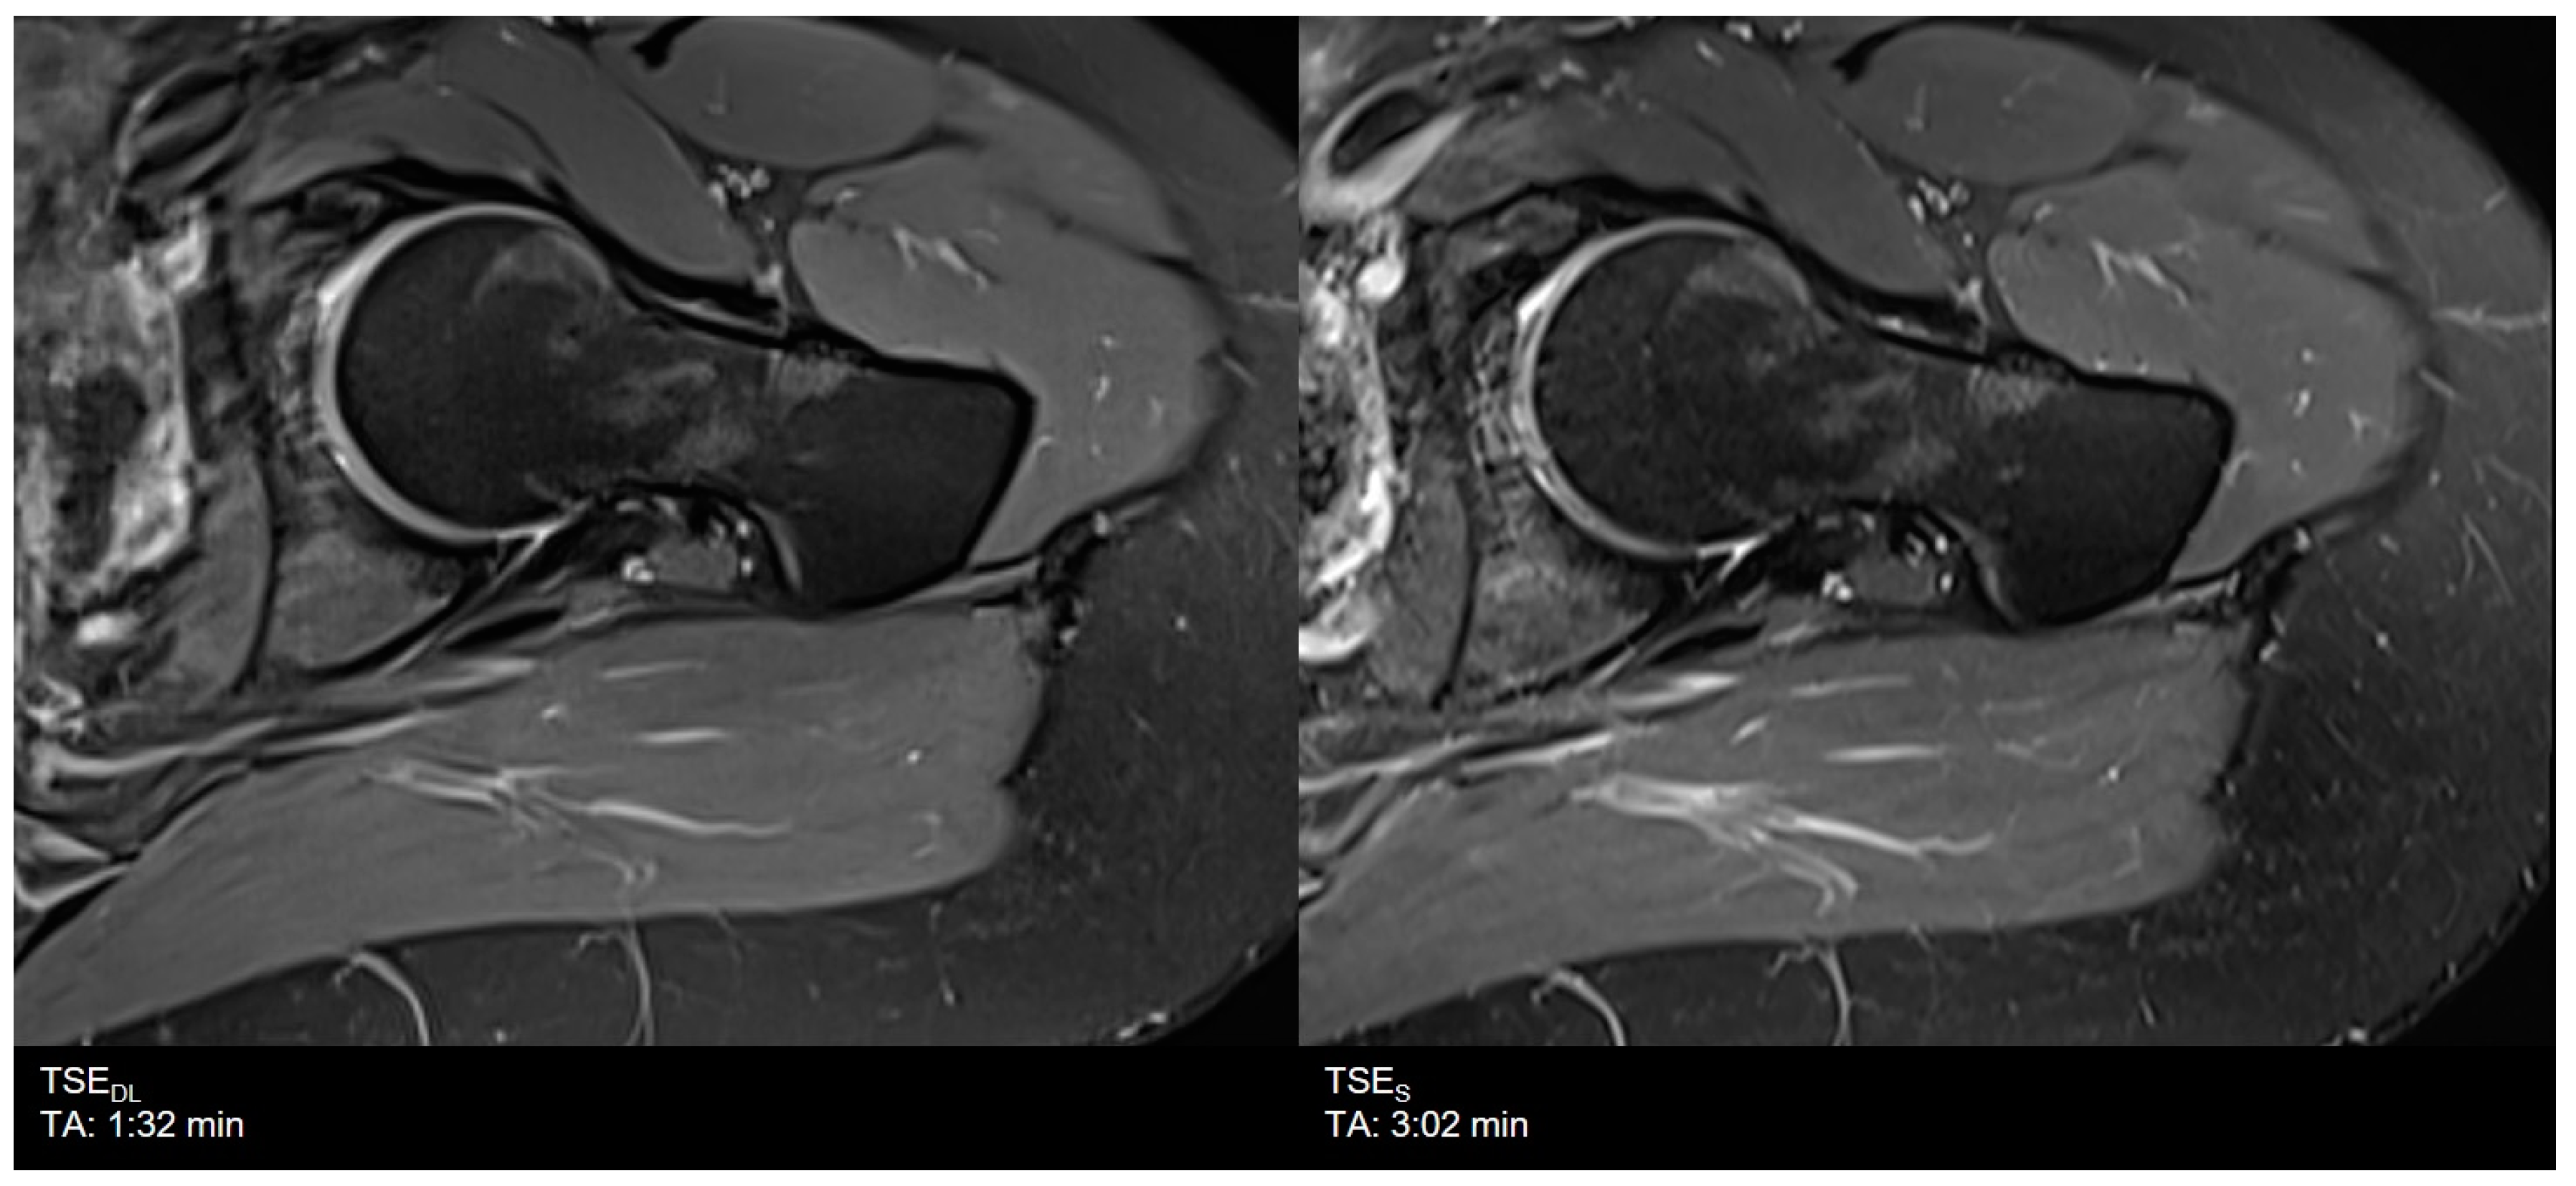

| Hip | TSES | TSE PD FS | axial | 3:02 | 200 | 0.3 × 0.3 × 3.0 | 1 | 1 | 0 | 3410 | 42 | 150 | 100 | 14.1 |

| TSEDL | TSE PD FS | axial | 1:32 | 200 | 0.6 × 0.6 × 3.0 | 1 | 1 | 3 | 3069 | 42 | 150 | 120 | 13.1 | |